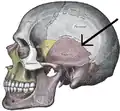

The squamosal suture, or squamous suture, arches backward from the pterion and connects the temporal squama with the lower border of the parietal bone: this suture is continuous behind with the short, nearly horizontal parietomastoid suture, which unites the mastoid process of the temporal with the region of the mastoid angle of the parietal bone. The term parietotemporal suture may refer to both of these sutures or exclusively to the parietomastoid suture and its use is, therefore, best avoided.

Side view of the skull. Squamosal suture indicated by the black arrows.